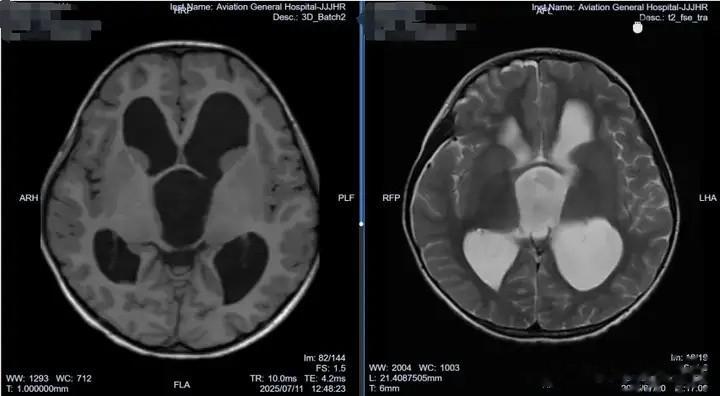

2024年6月,3岁的小妍(化名)在睡眠中突发全身抽搐,表现为颜面部肌肉及肢体节律性痉挛式抖动,呼之不应,持续时间约 8-9 分钟。紧急送往当地医院后,测体温 38.3℃,被考虑为 “高热惊厥”,给予镇静、退热治疗。随后的头颅 CT 及 MRI 检查发现脑室系统明显扩张,当地医院建议行脑室腹腔分流术,但小妍父母因担忧终生带管风险选择保守观察。2025年4月,小妍再次出现类似抽搐症状,复查显示脑积水持续存在。小妍父母了解到北京航空总医院的肖庆教授是治疗脑积水等相关疾病的专家,慕名前往北京求医。

肖庆主任详细查看小妍的影像资料后指出,这并非普通的脑积水,而是由于鞍上池囊肿堵塞了脑脊液循环通路所致。鞍上池位于颅内脑脊液循环的关键通路附近,当囊肿增大时,可能直接压迫或阻塞脑脊液的正常循环通道,导致脑脊液无法顺利从脑室系统流向蛛网膜下腔被吸收,从而形成梗阻性脑积水。如果直接进行脑室 - 腹腔分流手术,而忽略了鞍上池囊肿占位的情况,会使原本的制约关系失去平衡,脑室压力降低的同时,可能导致蛛网膜囊肿加剧扩张,往后处理会越来越棘手,还增加了分流术后的并发症风险。

肖庆主任建议采用软性神经内镜手术来解决囊肿问题。软性神经内镜手术具有创伤小、视野清晰、可灵活到达病变部位等优势,骨孔直径不到 1cm。在完善脑电图等检查后,于既定手术日,肖庆主任团队为小妍在全麻下行神经内镜检查术 + 脑室 - 囊肿 - 基底池造瘘术,术后病情平稳,复查MRI显示:脑室回缩、囊肿塌陷,于术后一周好转出院。